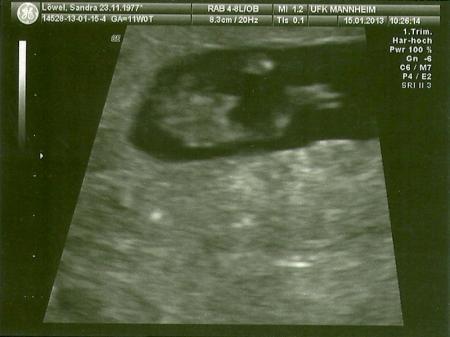

Ich hatte heute meinen Termin in der Klinik, mit dem Knirps ist alles gut, hat voll rumgezappelt, so daß der Doc meinte wir bekommen einen Tanzbären. Er hat nach Gesichtsmerkmalen geschaut und sich lange mit uns unterhalten, wegen gentischer Beratung, FWU und der gleichen, aber wir wollen nur auch den FUS zurückgreifen. Wir haben sogar ein 3D Bildchen bekommen und zum Schluß meinte er noch, der Kleine hat einen Zipfel, davon haben wir auch ein Bild bekommen. In 5 Wochen soll ich wieder kommen. LG ein paar Bildchen häng ich euch an.

Bild zu Heute Klinik - Forum für August - Mamis